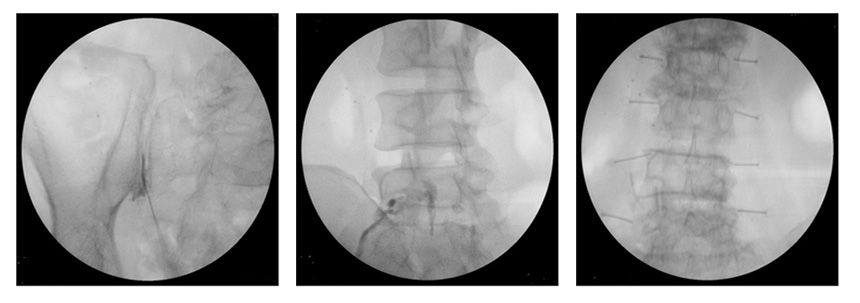

● 진단 추간판 탈출증 진단하기 위해서는 기본적인 X-ray촬영을하고 하지직거상검사를 통하여 통증발생 여부를 검사하고 감별하여 CT 및 MRI검사를 통하여 진단을 합니다. ● 치료 비수술적 치료는 약물치료, 물리치료를 하며, 증상이 계속 나타나는 경우에는 신경차단술을 시행하여 증상이 완화가 될 수 있습니다. 약물치료, 물리치료, 신경차단술을 시행하여 증상이 지속되는 경우 추간판 절체술, 후궁절제술을 수술적 치료를 시행하 여야 합니다. X선 투시촬영장치로 사용한 신경차단술 시술사진 ![]() |